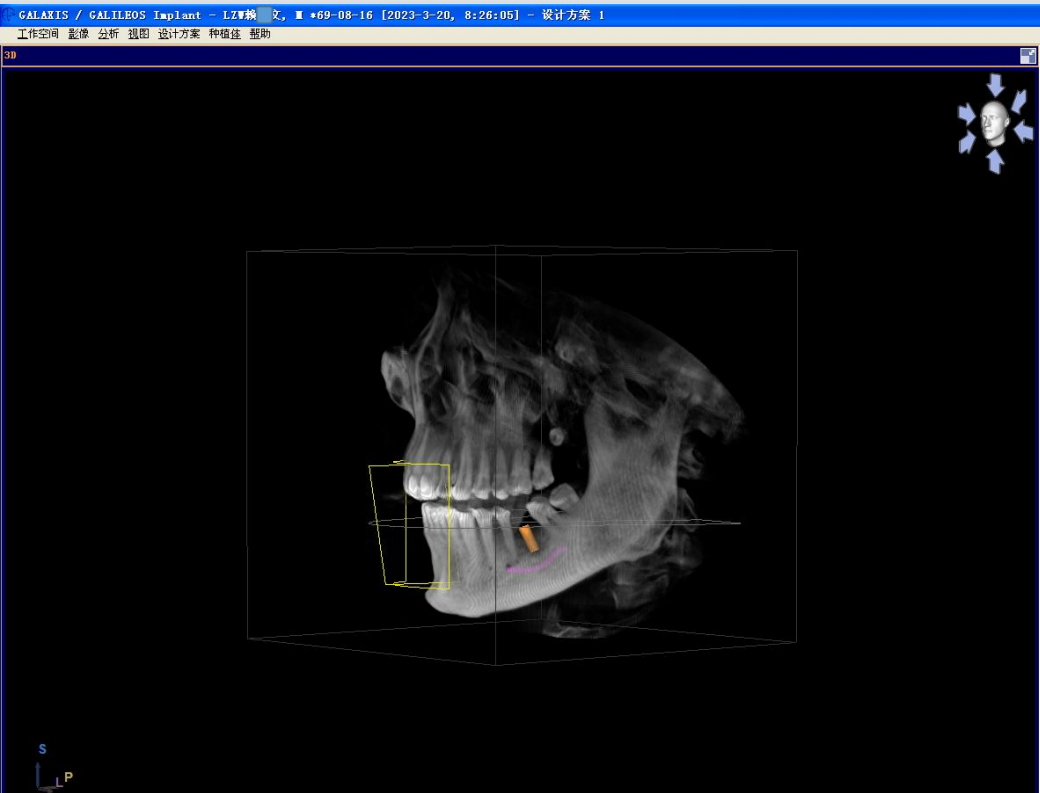

颊舌向宽度约7-8mm,骨质正常,无疏松影,35根尖远中见一"骨岛"影像